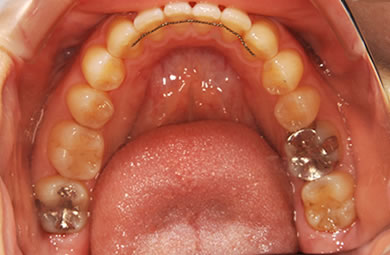

| 性別/年齢 | 女性 / 24歳 | ||||||||||||||||||||||||||||||||

| 治療方針 | 舌が横にはみでて、上下の歯が全く咬んでいない状態です。口元はきれいなので、歯は抜かずに歯列を少し横に広げて並べます。ゴムを使用したり、舌を訓練したりとても協力が必要な症例です。 | ||||||||||||||||||||||||||||||||

| 治療内容 | 唇側矯正(ホワイト)、保定装置 | ||||||||||||||||||||||||||||||||

| 治療期間 | 9ヶ月 |